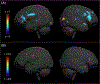

Lower white matter volume in beta-thalassemia associated with anemia and cognitive performance